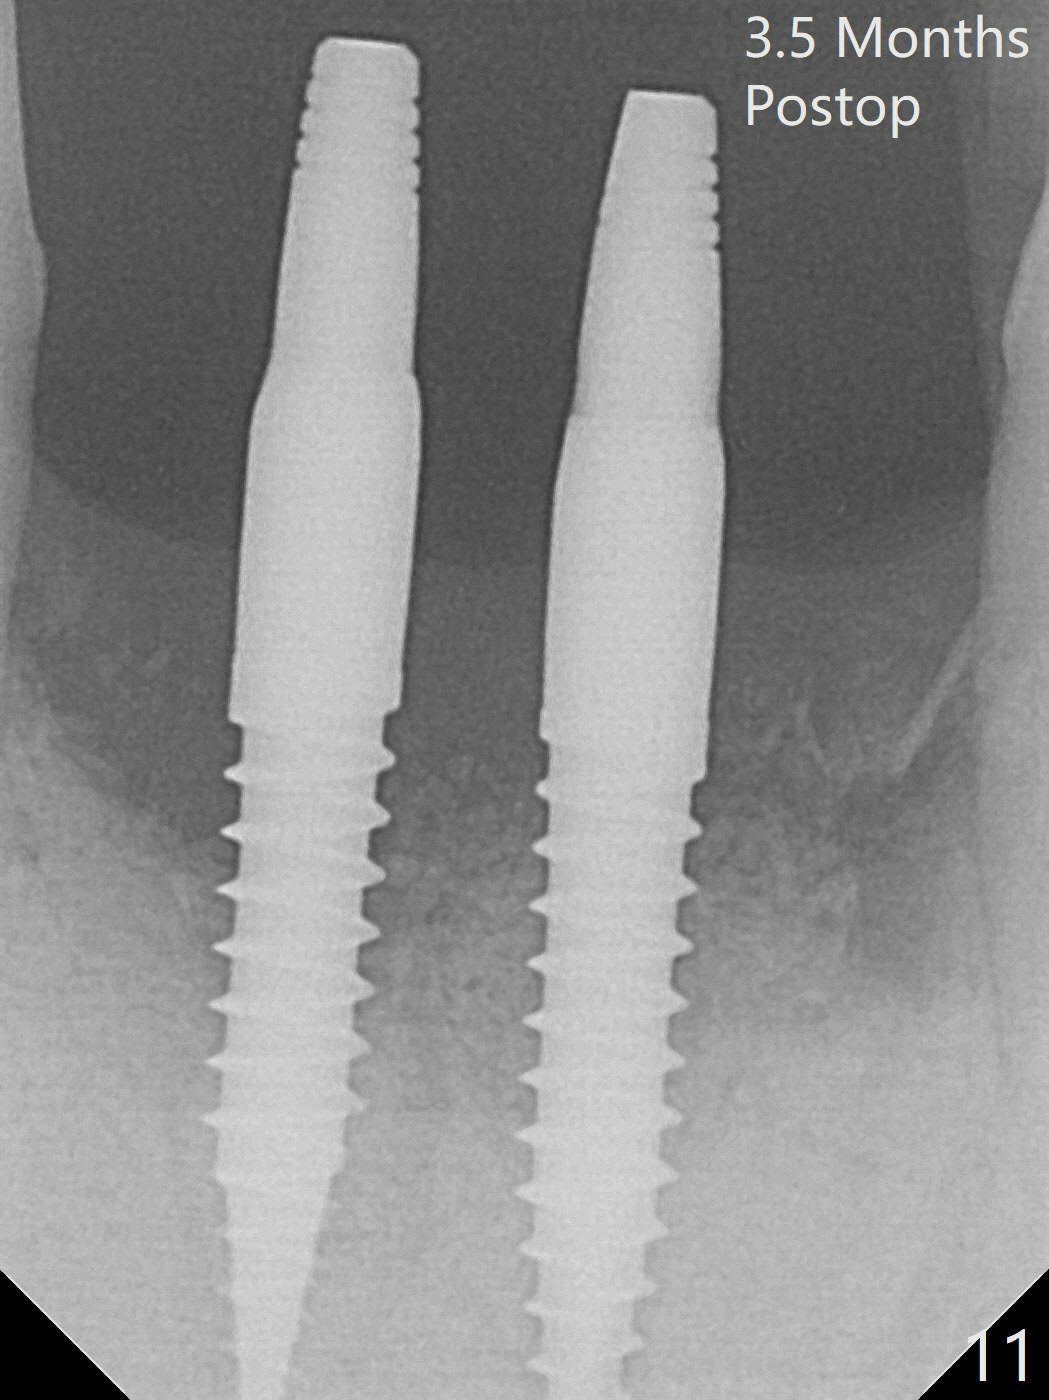

When the patient (smoker) returns for treatment, the apical abscess associated with #25 and 26 reduces with oral Amoxicillin. He agrees with 4 incisor extraction because of 2 apical fistulae (Fig.1 >). Osteotomy starts at the central incisor sockets due to mesial root exposure of the canines (Fig.2 arrowheads) and buccal alveolar bone fracture between #23 and 24 (Fig.7). Two of 3x14(4) mm 1-piece implants are placed with ~ 2 mm buccal gap (Fig.3). After Vanilla graft is placed in the bony defects (Fig.5 *) and Osteogen plug, sutures are placed (Fig.4). The implants are then placed deep to decrease thread exposure (Fig.6). Periodontal dressing is applied instead of provisional. Alveolar bone fracture between #23 and #24 accounts for why an implant is less suitably placed at #24 (Fig.7). Three months postop, composite is added to the pontic areas of the provisional (Fig.8 *). When the provisional is seated, the convex pontics press the used-to-be-flat gingiva (Fig.9 arrows). Thus the concave gingiva forms (Fig.10 *) with corresponding papillae (^). In fact the photos of Fig.8-10 is taken ~3 weeks later. Most of the grafted bone remains in place 3.5 months postop (Fig.11). A piece of floss with 2 knots in one end is placed between the middle units of the final bridge before cementation (Fig.12 (4 months 10 days postop)). In fact removal of residual cement is not so simple. It is tedious (Fig.13,14). An asymptomatic buccal fenetration with implant thread exposure is found 2 months post cementation and persists for another month in spite of advice to reduce smoking (1/2 ppd) and use of water pik (Fig.15). The area will be debrided, followed by bone graft and PRF in a month.